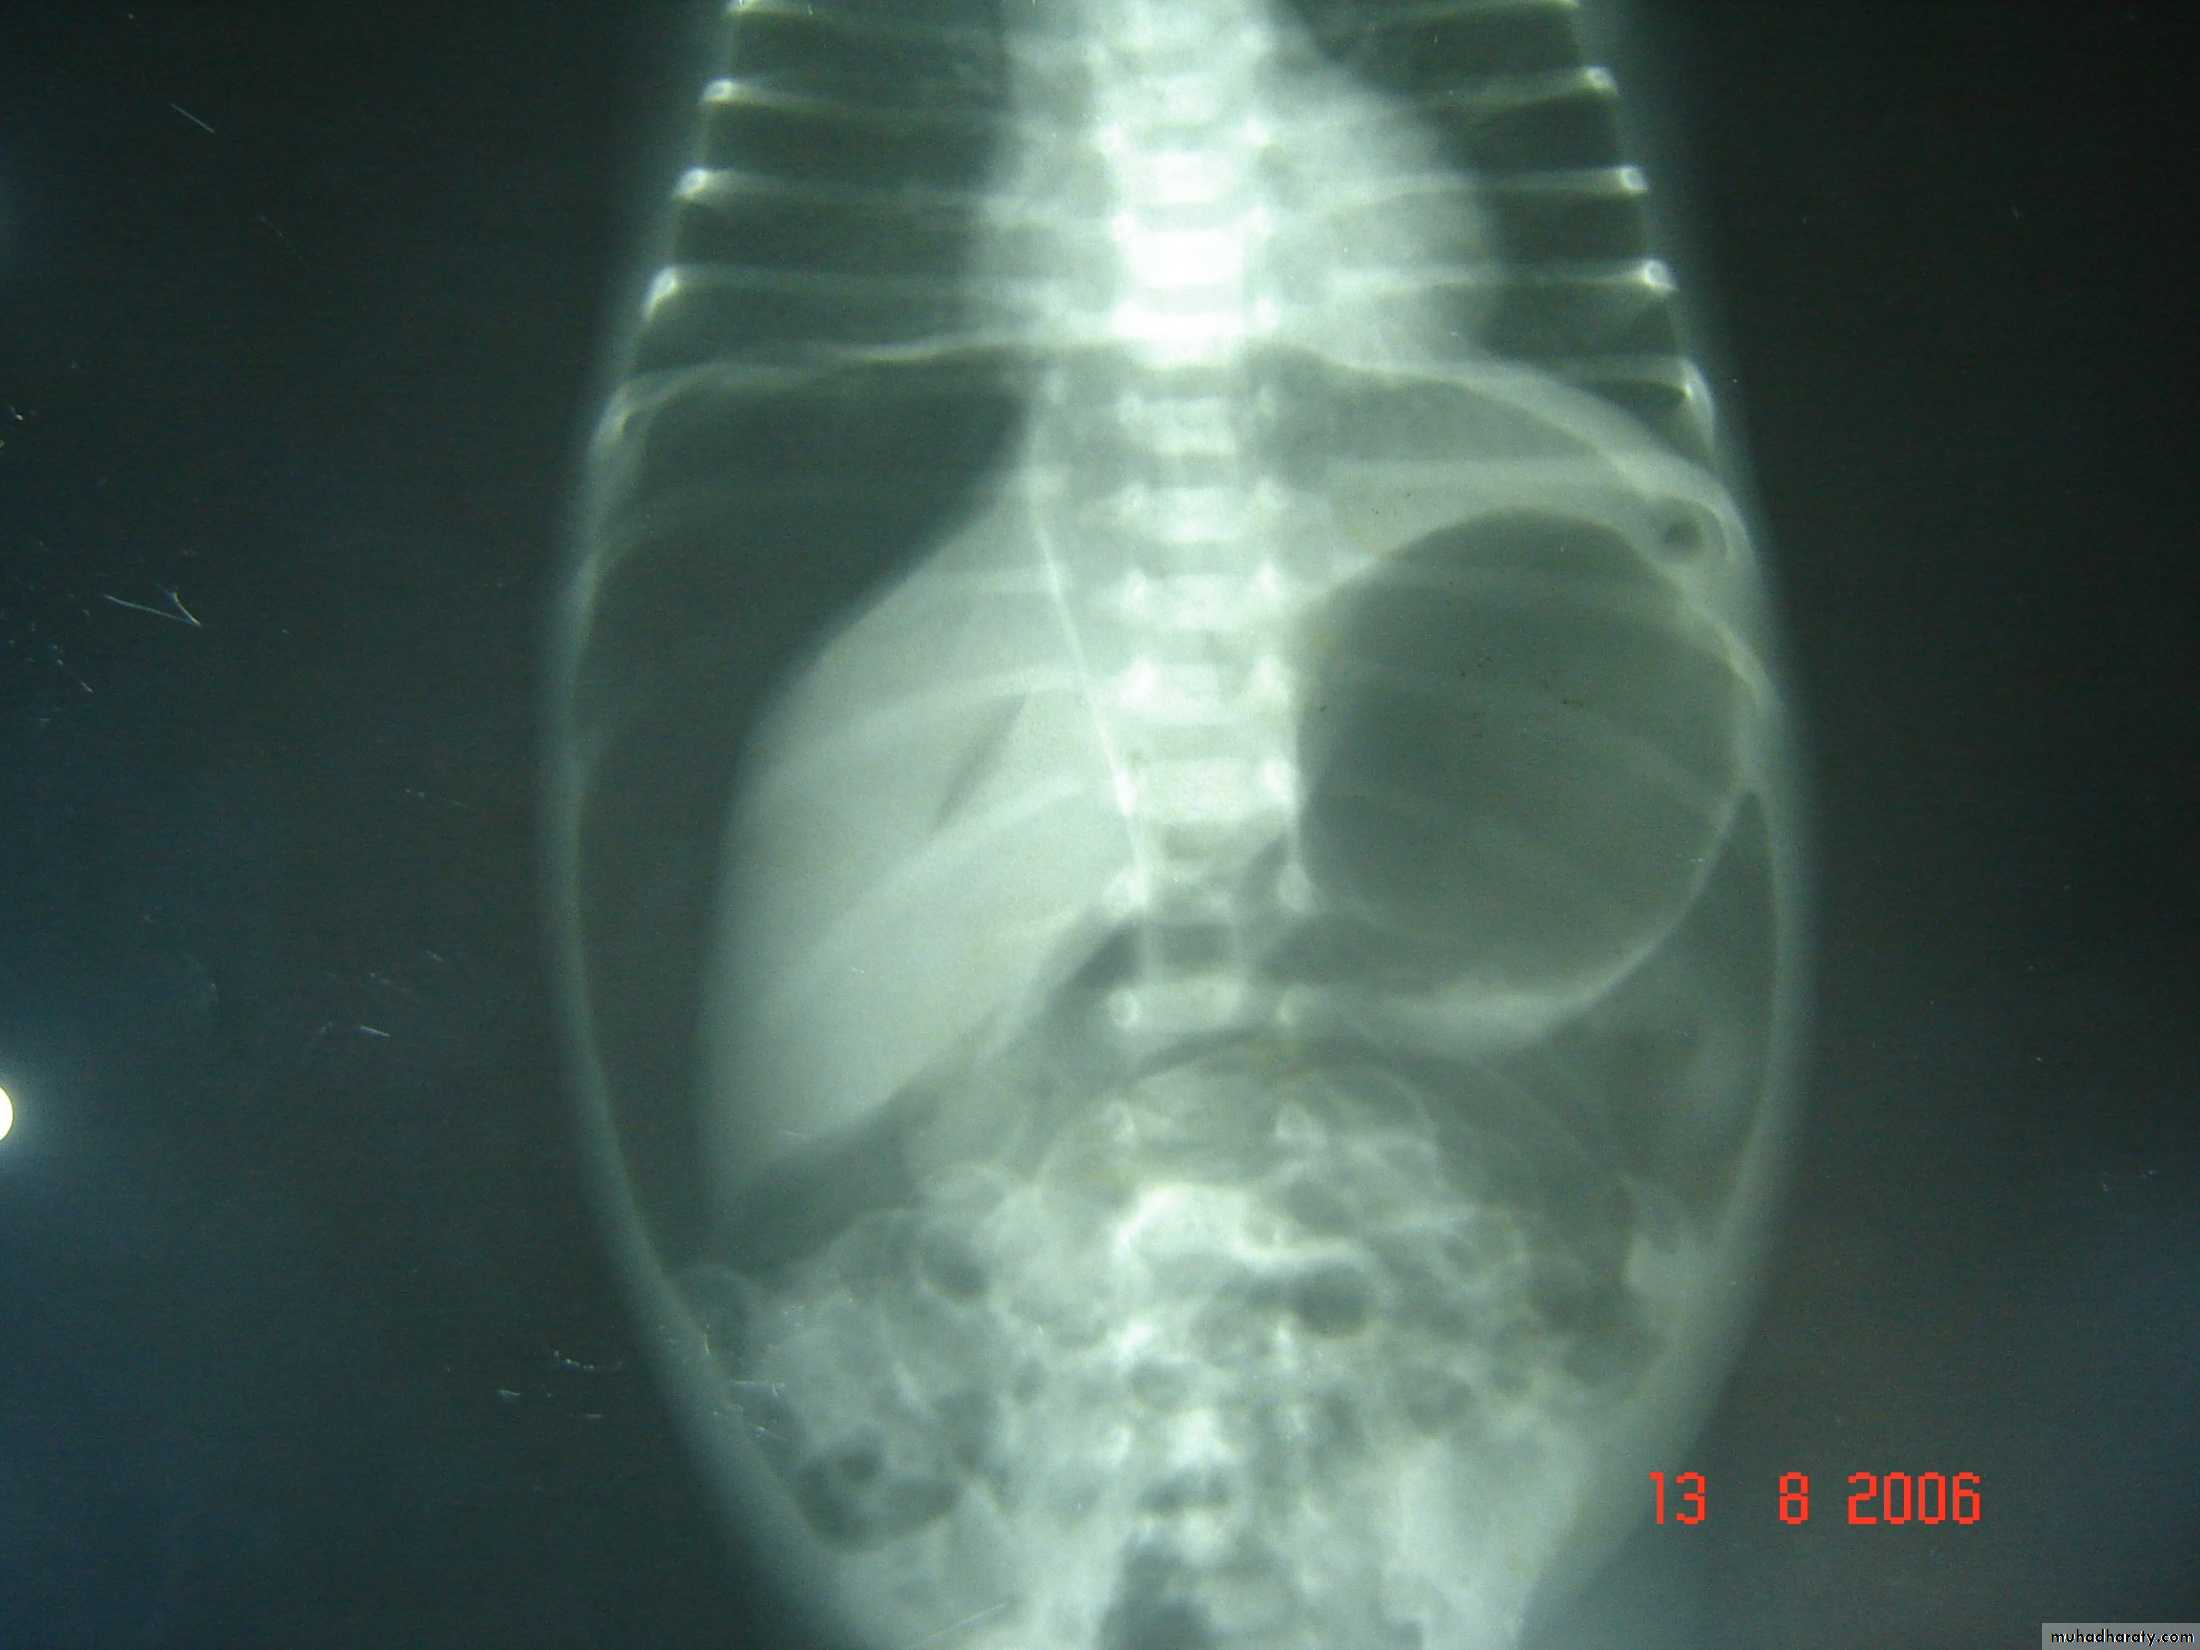

Bowel Obstruction

N.E.C